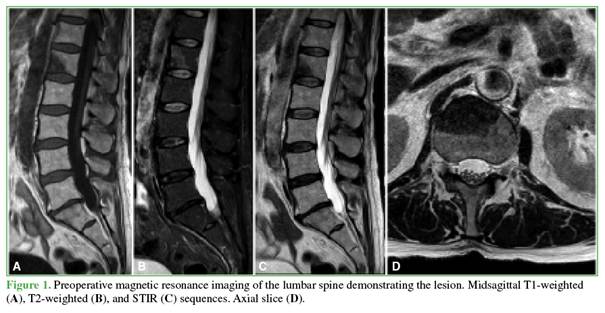

Preoperative images

Figure 1 shows preoperative magnetic resonance imaging of the lumbar spine, including midsagittal T1-, T2-, and STIR-weighted sequences, as well as an axial slice at the level of the L1 vertebral body. A lesion is observed compromising the vertebral body structure and predominantly involving the anterior column at the L1–L2 segment, without spinal canal involvement. The lesion appears hypointense on T1- and T2-weighted sequences and hyperintense on STIR images.